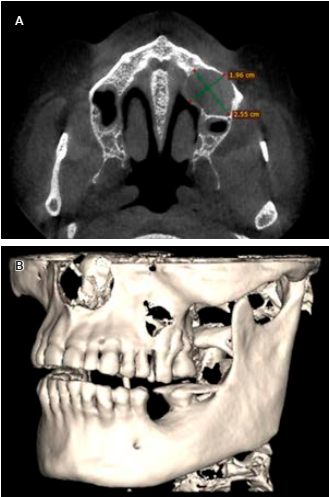

72 years old male was referred to the Facultad de Odontologia, Universidad Autónoma de Guadalajara for routine evaluation. On physical examination there was an asymptomatic patientwith preserved oral cavity, normochromic mucosa, and symmetric bone structure (Figure 1). Routine orthopantomography was requested and it demonstrated a radiolucent left maxilla region, molars and pre-molars (Figure 2). By to computed tomography (CT) with 3D reconstructionshe showedhypodense circular area (1.9 × 2.5 × 2.0 cm) with defined edges (Figure 3A) communicated with the nasal cavity, osteolysis in the palatine region and the anterior wall of the left maxilla (Figure 3B).

Figure 3 Computed tomography scan cut axial facial (CT) shows. A) Radiolucent circular area in left maxillary sinus of 1.96 × 2.55 cm. B) Bone destruction in the anterior wall of the left maxillary sinus.